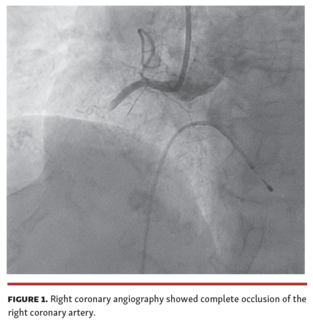

Andrea Ascione, MD; Alessio Arrivi, MD, PhD, FESC; Marcello Dominici, MD; Nicola Bier, MD

To our knowledge, this is the longest coronary thrombus ever reported to be removed in its entirety.